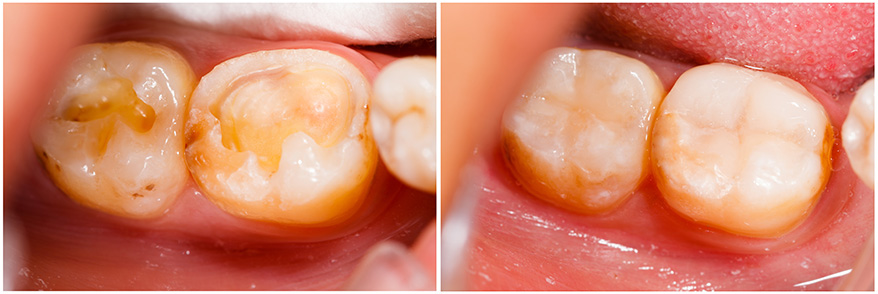

Resinas Dentales en Cancún

Las resinas dentales es la técnica  correspondiente cuando lo que se busca es una opción conservadora y estética para dientes que han sufrido caries o pequeñas imperfecciones.

Los dientes deteriorados por caries requieren ser empastados, las obturaciones (empastes) que se realizan son blancas y muy resistentes a la masticación.

Los empastes blancos están compuestos por resina que es un material sintético que se endurece una vez que se le aplica  luz halógena, los avances tecnológicos han hecho posible reconstruir dientes anteriores y empastar molares sin que se note, lográndose así estética y funcionalidad.

• Ya que se preparan al color del diente y por su apariencia natural, practicamente son imperceptibles.

• Mejoran la apariencia de los dientes fracturados o manchados.